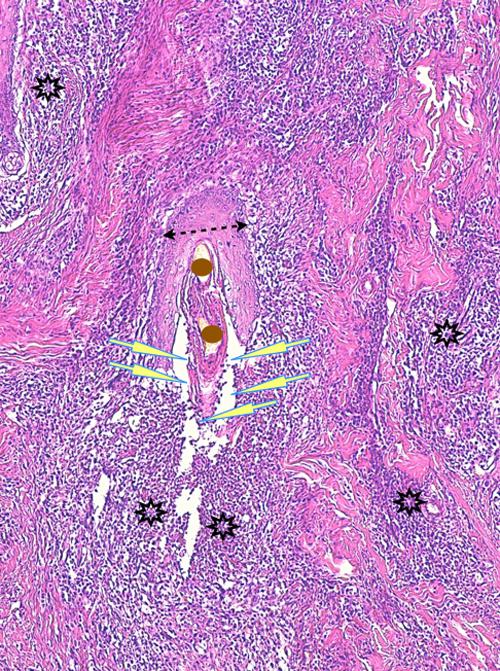

Photo 1 (Hémalun Eosine X 40) peau velue: L’épiderme et les infundibula folliculaires

sont hyperplasiques et hyperkératosiques. Les infundibula folliculaires sont le siège de pustules luminales et

pariétales, avec des fissurations linéaires parallèles au grand axe des follicules.

Le derme montre un inflammation péri-vasculaire et folliculo-centrée à diffuse.

Légendes de la Photo 1 :

- Double flèche bleue pointillée : grand axe des infundibula folliculaires à gaine épithéliale hyperplasique

- Double flèche verte : derme

- Ovales jaunes : pustules dans la paroi des follicules pileux

- Flèches jaunes : fissures linéaires dans la paroi des follicules pileux qui sont parallèles au grand axe des infundibula folliculaires

- Étoiles vertes évidées : lumière d’un follicule pileux hyperkératosique occupée par de la kératine et couche cornée hyperkératosique

- Étoiles rouges pleines : infiltrat dermique périvasculaire, périannexiel à diffus

- Étoiles turquoises pleines : lumière de follicules pileux obstruée de débris inflammatoires